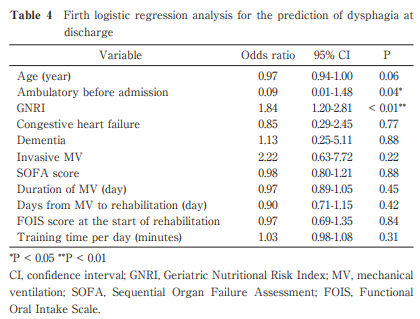

Investigation of the Predictors of Dysphagia in Cardiovascular Patients Treated with Invasive and Non-invasive Mechanical Ventilation

Tomoyuki Nakamura et al.

Published online : December 26 , 2024